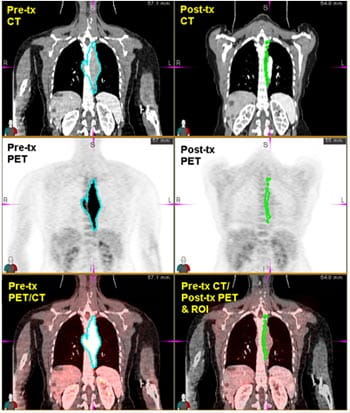

Services offered include an assortment of simplified imaging biomarker procedures depending on the needs of the researcher (Figures 3 and 4). Examples include assessment of static tracer uptake measures such as SUV, maximum SUV, and tumor glycolytic index (in the case of FDG). PET-CT scans of one patient at different therapy time-points can be registered together in order to evaluate therapeutic response over time.

Figure 3. One arm of the TIM analysis laboratory is the development of simplified, clinically practical methods for evaluating early-therapy response in cancers. Here, a 60 year old patient with squamous cell carcinoma of the head and neck (SSCHN) is demonstrating a large 3.3×2.3cm confluent nodal metastasis at left level II. Volumetric method of analysis (left) is performed by drawing a volume of interest (VOI) around the lesion and mirrored contra-lateral region is displayed here in a series of transverse slices. The baseline scan (right, top row) maximum SUV was 17.7 and the post therapy (right, bottom row) maximum SUV was 3 were found with conventional clinical ROI measurements. Total glycolytic index (TGI) was also measured at both time points. At baseline, TGI= 82.2 and decreased to 4.6 at post-therapy, which was within one SD of background FDG activity.

Figure 4. SUV threshold defined region of interest precisely translated to CT imaging at both baseline and therapy response.